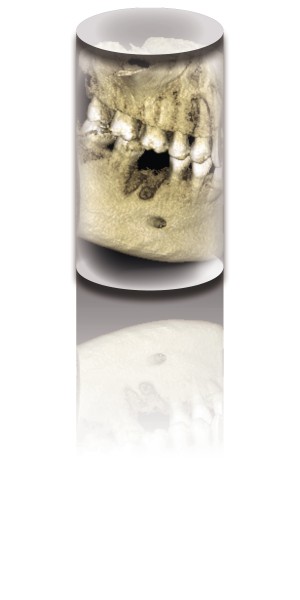

CBCT before endodontic therapy enables good planning and analysis with predictable outcomes. Especially helps in multi-rooted teeth, preventing from over-instrumentation, creating of ledge or separation of files.